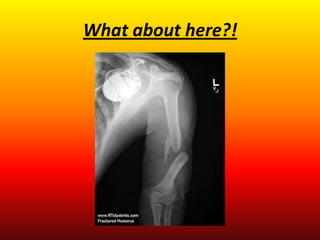

Carefully examine these xrays.

Can you determine which bone has been

broken or fractured?

Oh my! What have we here?!

What about here?!